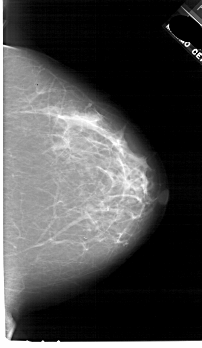

A_1763_1.LEFT_CC

LEFT_CC LINES 6871 PIXELS_PER_LINE 3931 BITS_PER_PIXEL 12 RESOLUTION 43.5 OVERLAY

FILE: A_1763_1.LEFT_CC.OVERLAY

TOTAL_ABNORMALITIES 1

ABNORMALITY 1

LESION_TYPE MASS SHAPE OVAL MARGINS ILL_DEFINED

ASSESSMENT 4

SUBTLETY 3

PATHOLOGY BENIGN

TOTAL_OUTLINES 1

BOUNDARY